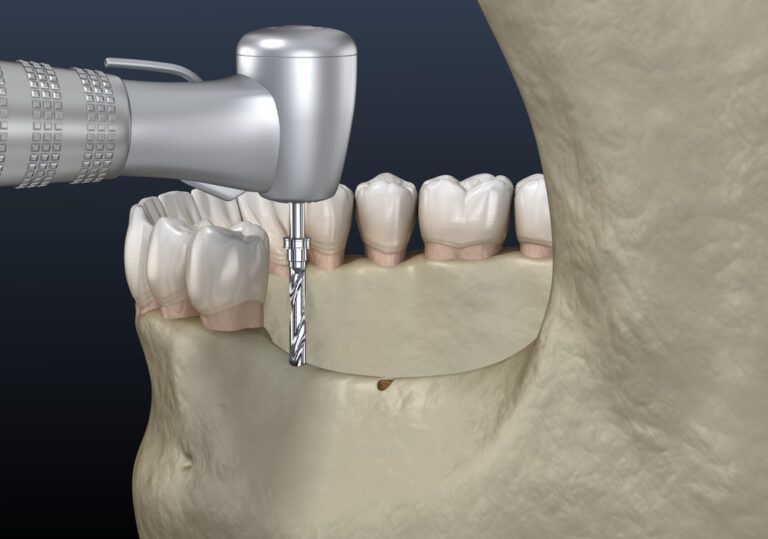

The Step-by-Step Process of Dental Implant Placement

Dental implants represent a groundbreaking advancement in restorative dentistry, offering a durable solution for replacing missing teeth and enhancing oral functionality. These artificial tooth roots, typically made from titanium, are surgically inserted into the jawbone, providing a strong foundation for